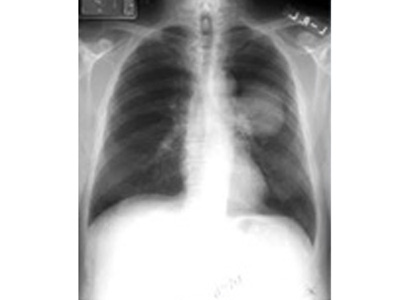

- Lung